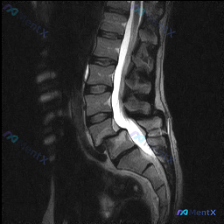

网上看到一份腰椎MRI T2序列的矢状位影像,用户第一句问的是「有没有脊柱侧弯」。 先不说结论,把影像里能看到的客观表现先列出来: - 下腰椎(L4/5、L5/S1)椎间盘T2信号明显降低,高度稍变窄,后缘有突向椎管的局限性影,压迫硬膜囊前缘; - 部分椎体终板有T2高信号,考虑Modic改变; -...

网上看到一份病例的影像讨论: 有人拿了一张腰椎矢状位T2加权MRI直接问「这张图有没有脊柱侧弯(Scoliosis)」。 先不说结论,先整理下这张图的主要影像表现: 1. 椎间盘:L3/L4、L4/L5、L5/S1信号明显降低(黑盘),L4/L5、L5/S1椎间隙轻度变窄,且这两个节段有明确的后方突...

整理到一份影像读片的病例资料,觉得很容易踩「诊断维度错位」的坑,放出来讨论一下。 先看核心情况: - 疑问是「从这张MRI能不能看到脊柱侧弯」 - 提供的是腰椎MRI T2加权矢状位图像 先附影像报告里的客观表现: 1. 椎间盘:腰椎各节段T2信号明显降低(脱水退变),L4/L5、L5/S1椎间隙狭...